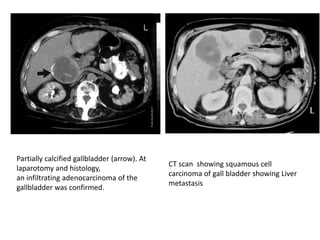

Partially calcified gallbladder (arrow). At

laparotomy and histology,

an infiltrating adenocarcinoma of the

gallbladder was confirmed.

CT scan showing squamous cell

carcinoma of gall bladder showing Liver

metastasis